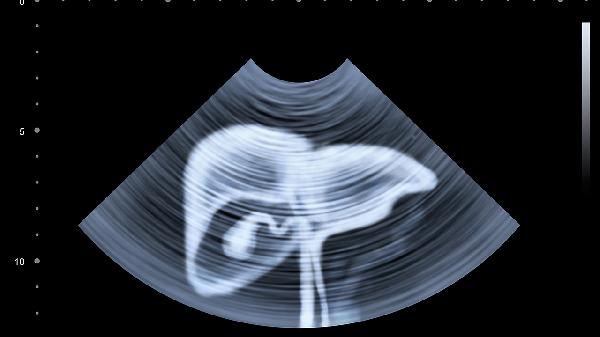

女性盆腔炎或子宫内膜异位症常引起下腹坠痛并向肛门放射。经期疼痛加重者可用暖宫贴,非经期持续疼痛需妇科超声排查附件包块。